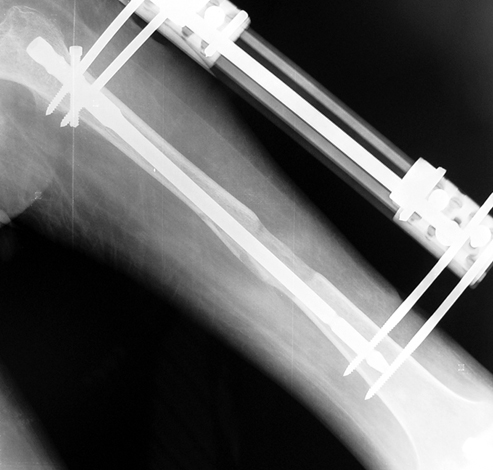

3. POSTTRAUMATIC LOWER LIMB SHORTNESS (MALUNION)

This type of shortness occurs after a fracture heals in a shortened position. Most cases are seen in adults and can be treated with one lengthening operation. Additional deformities can be corrected simultaneously. Most of these cases can be treated with lengthening over nail or just corrections and intramedullary nailing.